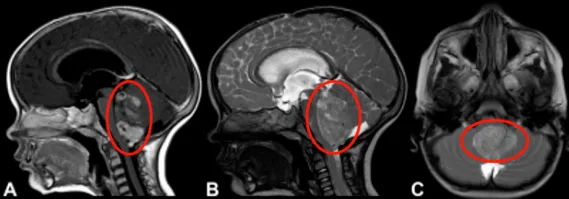

18个月大的安安,脑子里长了一个巨大的肿瘤。对普通人来说,这已经很难接受,对安安的家人来说更是晴天霹雳。安安开始频繁呕吐,吃不下任何东西,家里人看着孩子越来越消瘦,连忙带去做了头颅核磁检查。

报告出来,家人几乎当场崩溃。四脑室里有一个巨大的占位,肿瘤挤压着脑干,安安的情况刻不容缓。

手术那天,安安的家人在手术室外焦急等待,只希望孩子能平安出来。最后的结果,却让他们喜出望外。Rutka教授采用枕下开颅联合C1椎板切除术,成功将巨大室管膜瘤全切,手术过程中没有出现神经功能损伤。术后病理确认为间变性室管膜瘤。